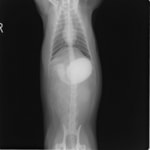

4歳 アメリカンショートヘアー

主訴:3日前から嘔吐が続き、食欲も落ちてきたのこと。

対症療法(症状に対する治療)に反応しないため、精査を実施。

一般血液検査:問題なし

単純レントゲン検査:胃内ガス陰影・腸内ガスが少量認められる。

嘔吐が改善しないため、消化管バリウム造影検査を実施。

以下、

消化管バリウム造影レントゲン

バリウム造影3時間経過するも、胃内からバリウム排泄なく同日内視鏡検査を実施。

内視鏡検査結果:内視鏡下にて、バスケット鉗子を用いて摘出。

症例は、机の上に置いていたピスタチオのお菓子を誤飲していました。その後の経過は良好です。本症例は、内視鏡下にて摘出ができましたが、球状・立体などの大きな異物は、腸の途中で詰まりやすく、内視鏡下での摘出が困難な場合もあります。その際は、開腹下にて腸内の異物を摘出しなくてはなりません。動物たちは、思わぬ物を誤飲することがあります。お留守番時・就寝時は、誤飲をしやすい時間帯ですので注意しましょう。